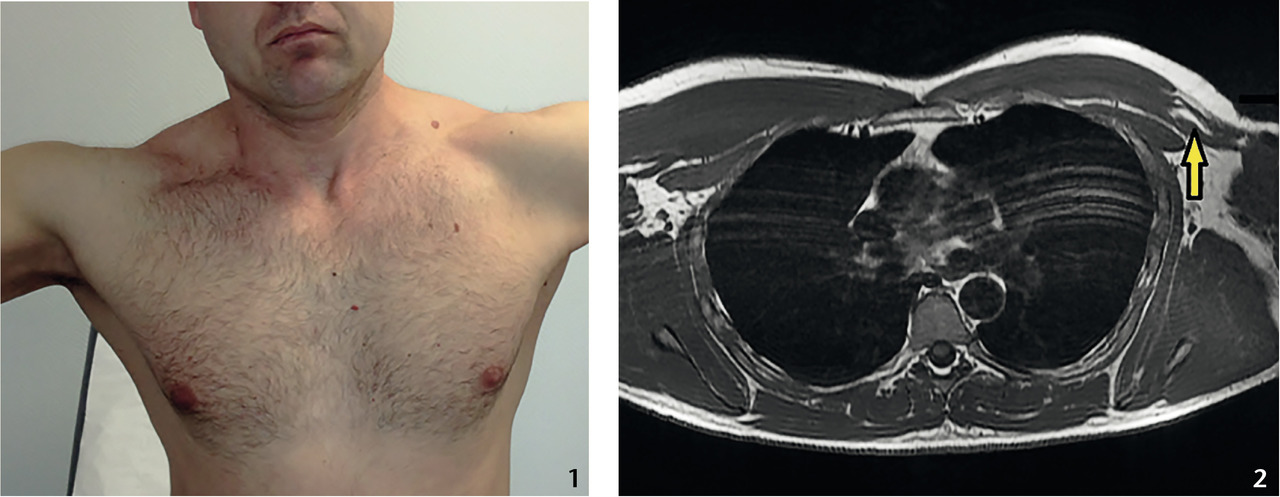

Quatre mois plus tard, il est revu en visite annuelle d’aptitude (fig. 1 ). À l’inspection, l’asymétrie du grand pectoral fait prescrire une IRM (fig. 2 ).

Quatre mois plus tard, il est revu en visite annuelle d’aptitude (